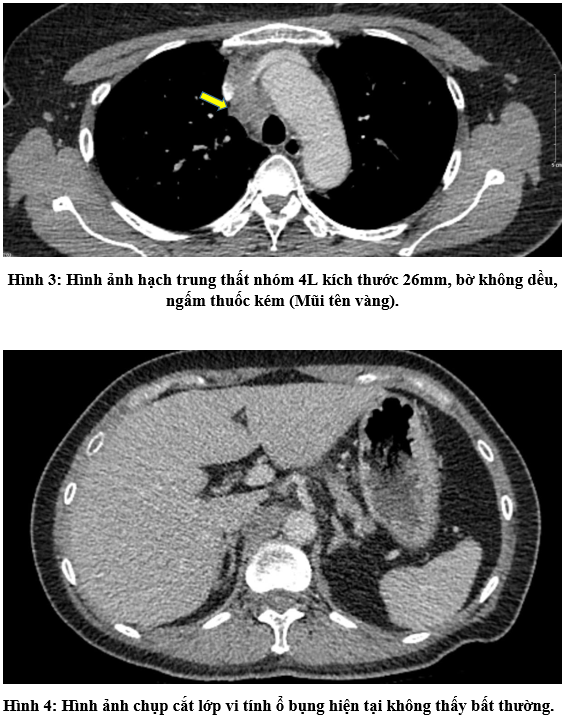

Ca lâm sàng:Hiệu quả điều trị đích bằng Osimertinib ở bệnh nhân UT biểu mô tuyến của phổi giai đoạn IV có đột biến gen EGFR L858R (Exon 21) tại Trung tâm YHHN&UB-Bệnh viện Bạch Mai

Ung thư phổi là một trong những ung thư có tỷ lệ mắc và tử vong cao nhất trên toàn thế giới. Theo GLOBOCAN 2022, ung thư phổi đứng thứ hai về số ca mắc mới với khoảng 2,5 triệu trường hợp mỗi năm và là nguyên nhân hàng đầu gây tử vong do...